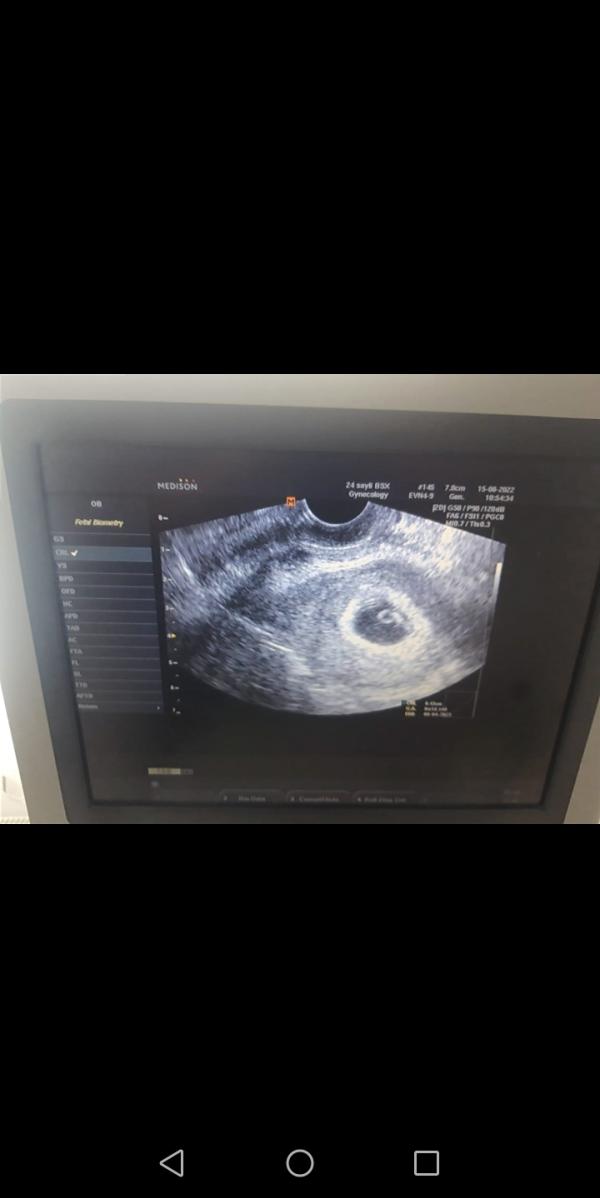

Сегодня был первый скрининг по УЗИ сказали что всё хорошо услышала сердцебиение 😭😭😭я там так разрыдалась 6 недель 1 день. Дата родов 9.04.2023..только сказали что есть тонус маленький прописали папаверин свечи 1 раз в день.